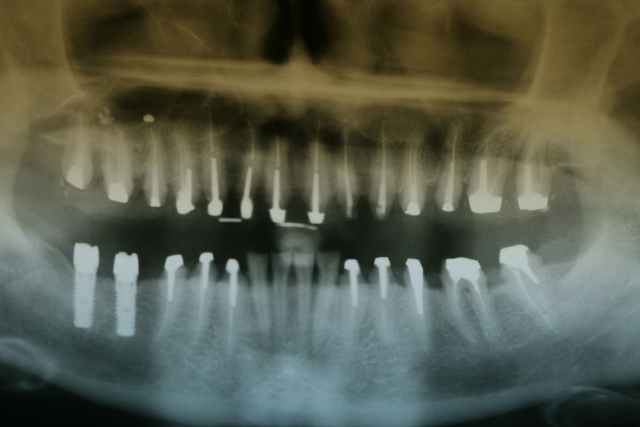

photos et pano du cas initial .

le cas commence en 2005.

Tout d'abord j'ai réalisé l'avulsion de 47.

empreintes d'études.

mise en articulateur programmable (SAMII)

puis goutière occlusale pour essayer de trouver une DVO semblant acceptable pour la patiente nous permettant de reconstruire dans des conditions esthétiques et fonctionelles.

réalisation des endos (atteintes pulpaires évidentes compte tenu du bruxisme) mars avril 2005

mai 2005 préparation des dents supports et mise en place des bridges provisoires haut et bas

toujours via le SAM II (au passage petite technique pour pouvoir conserver la DV en transférant de l'articu au vivant)

mise en place de deux implants en 46 47 juin 2005

octobre novembre 2005 réalisation des inlays cores

ci après pano et photos du bridges provisoires certes pas extraordinaires au niveau du ciment provisoire mais petite fatigue au bout de 4 heures de travail en bouche .